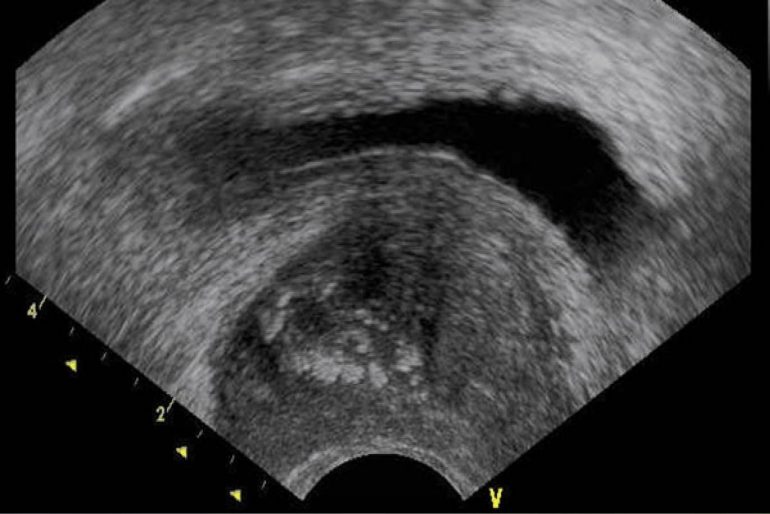

Las aplicaciones de la ecografía transrectal en el cáncer de próstata